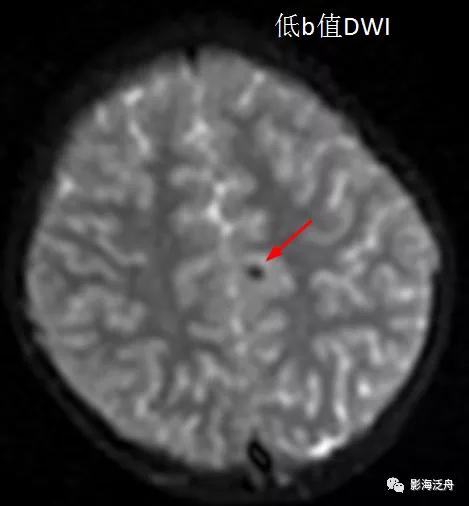

诊断虽然明确了,但故事到这里还没结束,回过头去看患者第一次检查的低b值DWI序列,可以发现这些病灶其实早就存在。但为什么第一次检查的时候没有及时发现呢?想必这大概率是因为大家对低b值DWI序列认识不足造成的,尤其是低年资诊断医生和神经科临床医生往往会自动忽略掉低b值DWI序列,再或者就是把低b值DWI误认为是高b值DWI序列。

在低b值DWI序列可以看到左侧大脑半球多发磁敏感伪影(红箭)。

笔者最近也看了一些文章,多数主张把低b值DWI序列当做是低配版的T2WI序列或是重T2WI序列,根据重复时间(TR)来看,这么解释确实没毛病,DWI的TR=3200ms,时间够长,也意味着T2权重够重。但问题是我们已经扫了标准的快速自旋回波T2WI序列,那么还有必要看这个模模糊糊的图吗?

以脑部常见的DWI序列为例,EPI是在单个SE序列(90°RF+180°重聚焦)之后采用梯度场的连续、快速、正反向切换来采集信号,由于整个成像过程只接受了一次脉冲激发,此外还要加上层面、频率、相位方向上三个互相垂直的梯度场,故而对局部微磁场的变化相当之敏感,且基础信噪比(SNR)奇低无比,所以DWI除了辨别组织有无弥散受限之外,还具有两个显著特点:一是容易形成磁敏感伪影(局部信号丢失/低信号),原因可以是出血、液体流动、软组织与气体交界面、钙化等;二是图像非常模糊。根据第一个特点,我们完全可以把DWI序列等价为一个低配版的SWI序列。